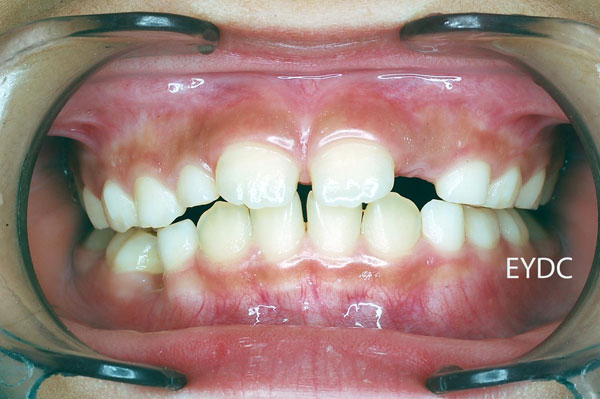

8才0ヶ月。上の前歯がハの字型に生えて来ました。でも何の心配もいりません。そのまま継続してください。

9才5ヶ月。だんだん大人の歯が生えそろって来ました。順調です。お菓子やアイスを控えて、歯磨きをがんばりましょうね!